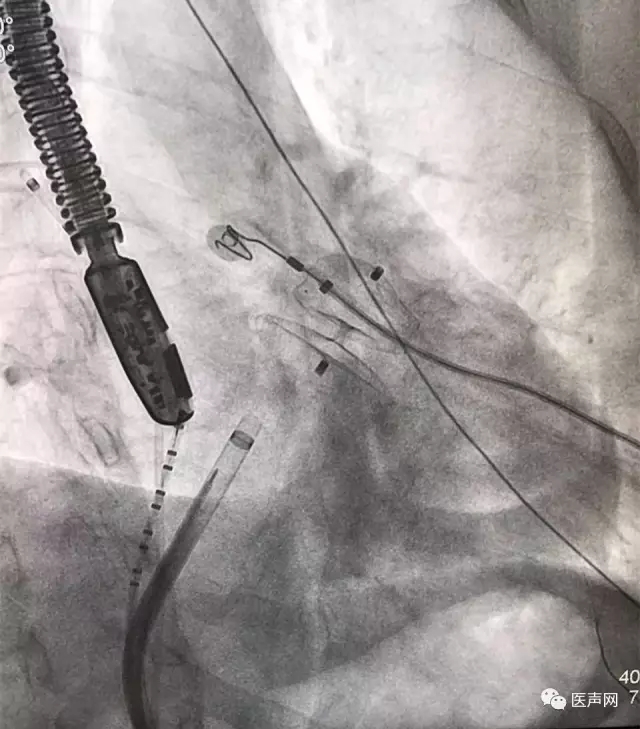

ACP放置